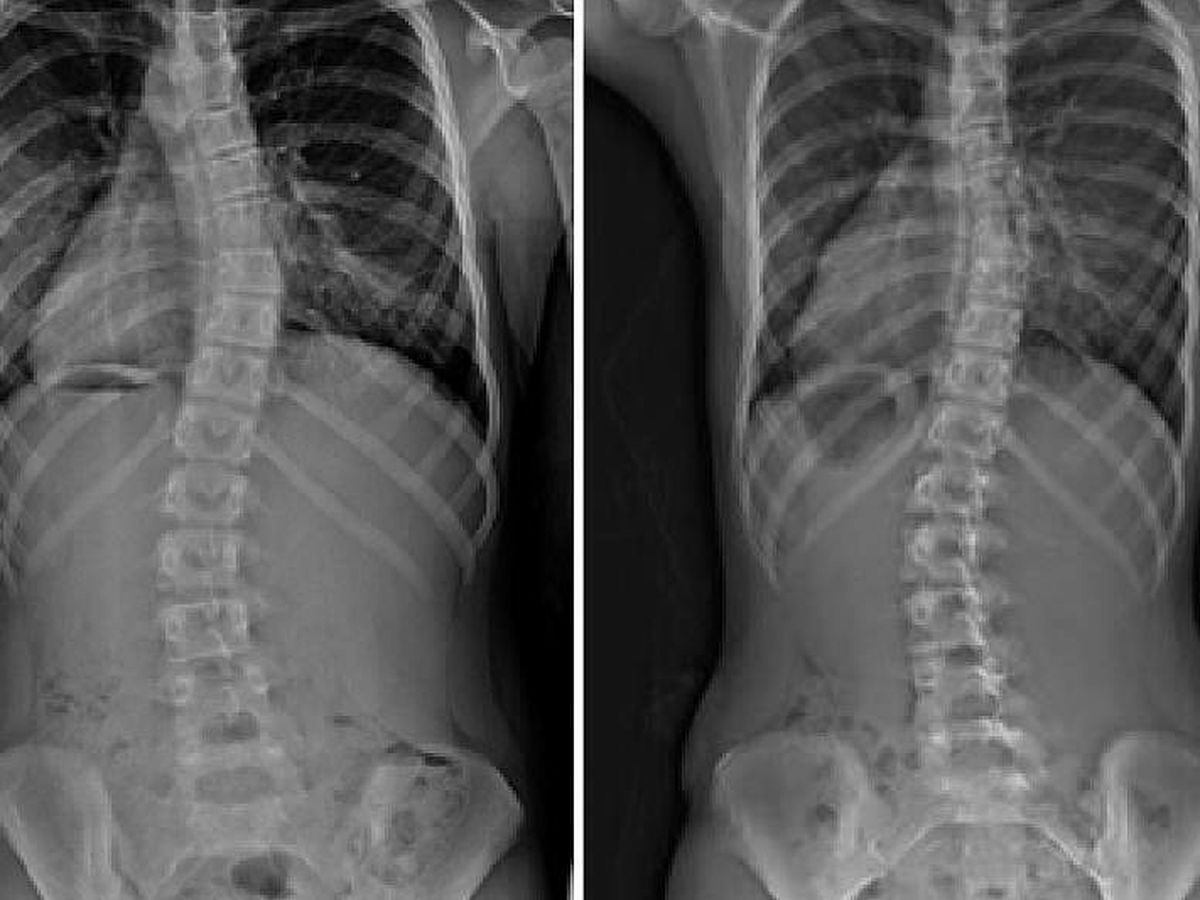

At 11years old, he has been diagnosed with a rare form of scoliosis.

His doctors have determined he will need to be immediately fitted for a brace that he will need to wear for 22 hours per day, (as an initial attempt to help correct his condition) with the possibility of additional treatment or surgery, due to the positioning of the syrinx in his spine and location of the curve.